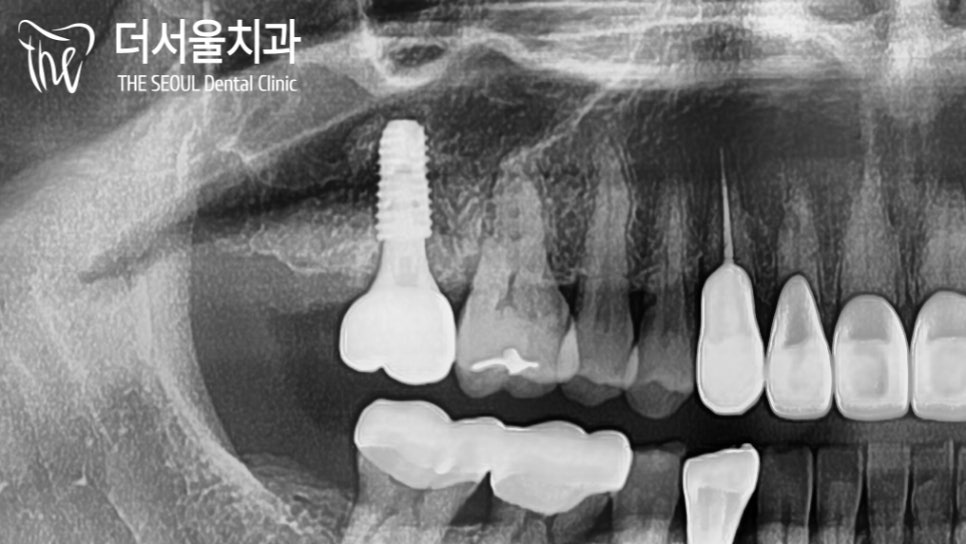

보다 정확하고 안전하게 심어져 있는

픽스처의 모습을 확인한 뒤

몇 달간 충분한 고정력을 가질 수 있도록

치유 기간을 부여하기로 했습니다.

파노라마 사진을 보면

튼튼하게 심어져 있는 상악 어금니 픽스쳐의

모습을 확인할 수 있습니다^___^

다행히 이번 치료도 성공적이었는데요.